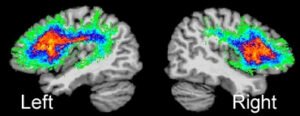

Por um lado, estudos de neuroimagem funcional vêm mostrando que a doença é causada por alterações anatômicas e funcionais do cérebro e, portanto, não se trata de uma fase do desenvolvimento da criança. Por outro lado, algumas hipóteses tentam justificar a disfemia.

A primeira delas refere que haja um excesso de dopamina nos núcleos da base, que são regiões do encéfalo que emitem e recebem projeções entre si e para várias outras partes do sistema nervoso central. A segunda hipótese é a de uma menor atividade lobo temporal esquerdo, parte lateral do cérebro onde fica o centro da linguagem, a Área de Broca.

Ao contrário do que muitos pensam, nosso cérebro não é simétrico. A linguagem, por exemplo, tende a ser mais ativa do lado esquerdo. Na gagueira, então, haveria uma hiperativação do lado direito em uma tentativa de compensar a baixa função do lado esquerdo.

Isso tudo contribui para a ideia de que pessoas com disfemia tenham pouca substância branca no cérebro. Enquanto a chamada massa cinzenta é composta pelos corpos dos neurônios, a parte branca é formada pelos seus axônios (a caudinha). Essas axônios, dessa maneira, são responsáveis por interligar as estruturas auditivas e motoras que coordenam todo o processo de ouvir, elaborar uma fala e dar o comando para os músculos da vocação. Poxa, um trabalhão né?